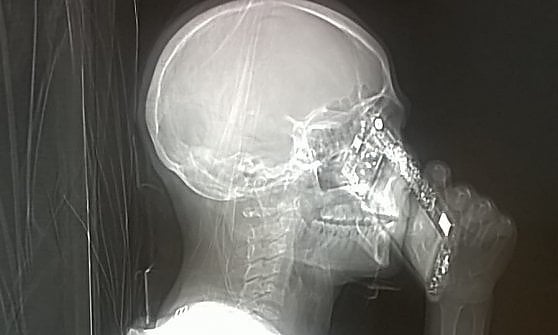

Una donna entra in TAC con il cellulare.

Nella società accelerata, l’avvento delle tecnologie digitali ha alterato la dimensione del tempo percepito (Gonidis e Sharma 2015). La diffusione degli schermi favorisce la proliferazione di testi, immagini, musiche, giochi, filmati, contenuti che si prestano a un consumo smodato e insaziabile. Lo zapping, le maratone youtube, il browsing compulsivo, il social surfing, pratiche consolidate nella comunità web, condividono una struttura del tempo percepito basata sullo schema breve/breve (Rosa 2015). Saltando di link in link, il tempo dell’esperienza accelera fino ad azzerarsi; il tempo dell’esperienza dunque è breve. Al termine della sessione, malgrado l’eventuale intensità degli stimoli psicologici ed emotivi, non sapremmo ricostruire l’esatta cronologia delle nostre visite, né rievocare con esattezza il vissuto esperienzale; anche il tempo del ricordo dunque è breve. A questa particolare configurazione del tempo percepito do il nome “cronocidio.”